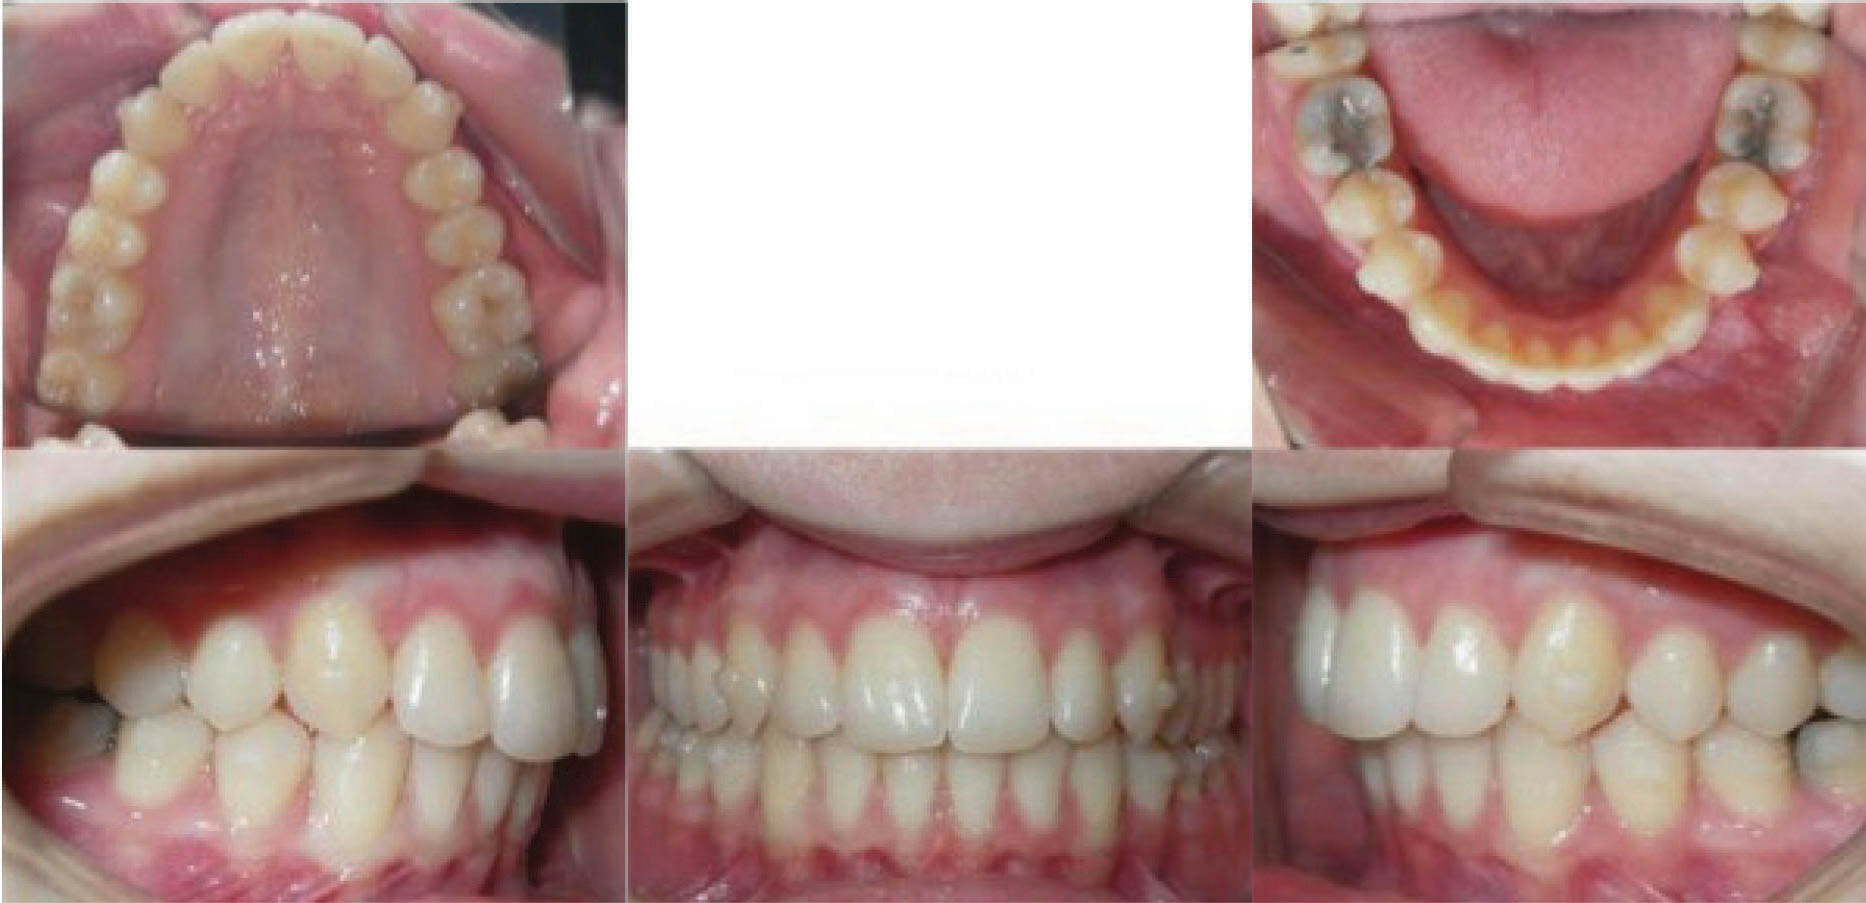

در انتهای درمان هم کرادینگ خوب درمان شد و هم رابطه مولری درست گردید (شکلهای 95-۶ الی 97-۶). عکس OPG طبیعی و سوپرایمپوز نمودن عکسهای لترال سفالومتری نشاندهنده پروترود شدن انسیزورهای بالا و پایین میباشد.

نکته: همانطور که در مقالات در اول مبحث بیان شد، موقعیت مولر بالا و نقطه A در طول درمان فرقی نمیکند. این تغییرات مانند استفاده از هدگیر است در حالیکه با الاستیک کلاسII بدست آوردهایم. ضمناً رشد مندیبل و قدامیتر قرار گرفتن نقطه پوگونیون هم مشخص میباشد و منجر به کاهش تحدب صورت گردیده است.

نتیجه: طول درمان ۲۸ ماه با دو قالبگیری مجدد و الاستیک کلاسII ۲ انسی بود.

شکل 95-6

شکل 96-6

شکل 97-6بررسی یک مورد